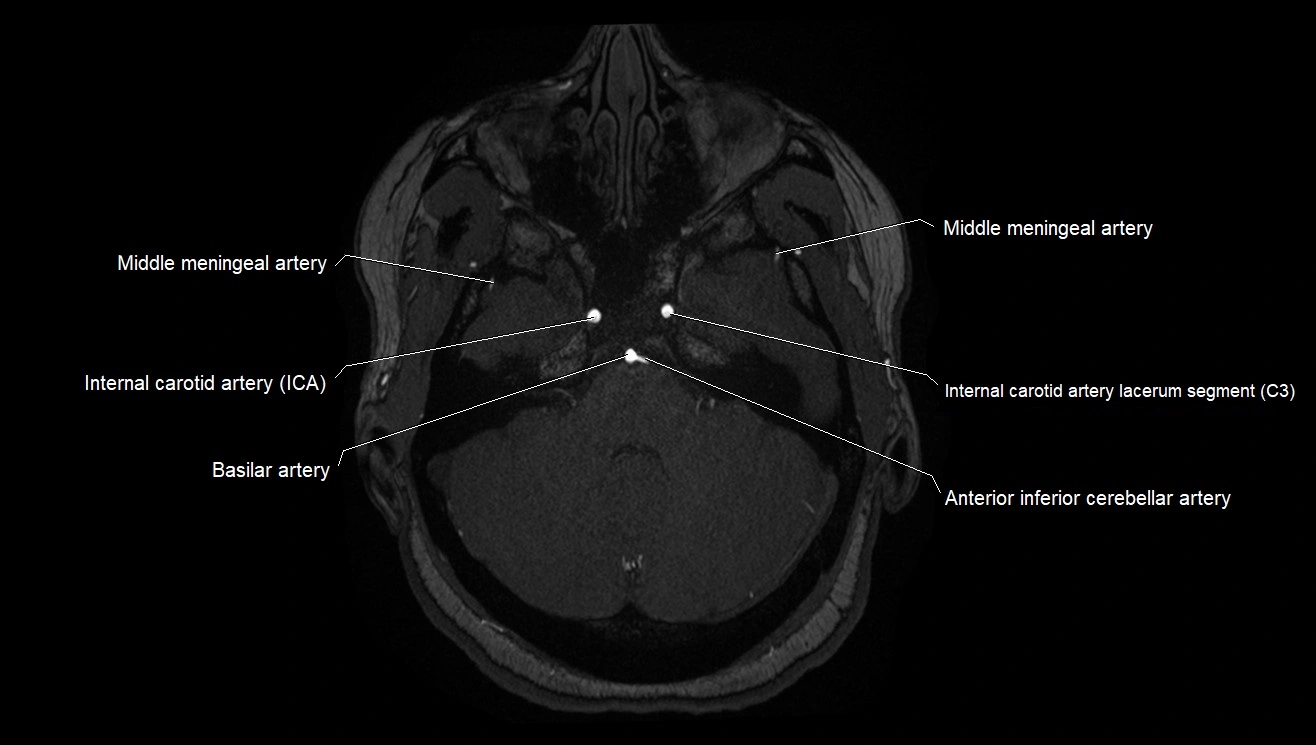

CT images

image